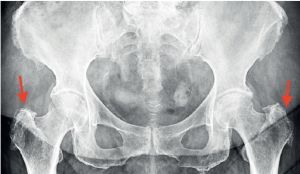

Fig. 2

Greater trochanter pain syndrome in standing pelvic X-ray (indicated with red arrows) – uneven outline of the greater trochanter, visible calcifications and osteophytes on the right and left sides.